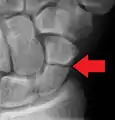

A more obvious scaphoid fracture on a scaphoid view X ray

Radiolucency around a 12 days old scaphoid fracture that was initially barely visible.[13]